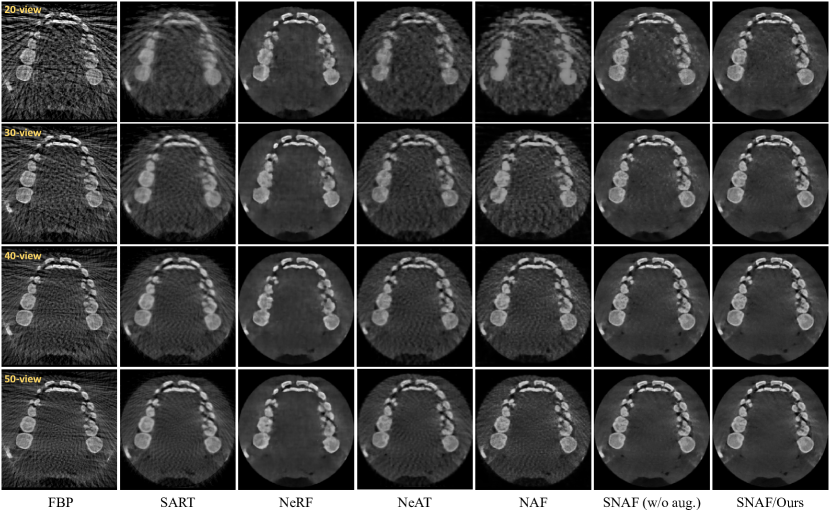

Refer to caption

Figure 4: Qualitative comparison with different methods. We compare the performance of CBCT reconstruction with different input views (each row), and visualize slices of the reconstructed 3D volumes from different methods (each column). Our reconstructed quality dramatically outperforms all other methods. For reference, please see the ground truth in Fig. 1 (axial slice).

To validate the advantage of our method, we compare the our SNAF with both learning and non-learning methods, including Filtered Backprojection (FBP)  [8], simultaneous Algebraic Reconstruction (SART)  [1], and three recently popular neural rendering solutions [13, 17, 23]. Specifically, FBP and SART are two traditional methods that are still commonly used in commercial CBCT systems, where FBP has high efficiency and SART is mainly designed for sparse-view CBCT reconstruction. The neural rendering approach, Neural Radiance Fields (NeRF) [13], is mainly designed for novel view synthesis in natural scenes, and we slightly modified it by removing its color prediction branch. Furthermore, we also compare two concurrent neural volume rendering methods, Neural Adaptive Tomography (NeAT) [17] and Neural Attenuation Field (NAF) [23], which are specifically designed for CBCT reconstruction with state-of-the-art performance. For ablation purpose, we present a variant of our SNAF by removing the view augmentation, denoted as SNAF (w/o aug.). The experiments are conducted in different numbers of input views (i.e., 20, 30, 40, and 50 views). Note that, 20-view is extremely sparse, and usually 25 times fewer than clinical collections.

Qualitatively, typical examples are displayed in Fig. 4, where it can be easily observed that our proposed method outperforms all competing methods, reconstructing CBCT images with more details and less noise. Specifically, since FBP only performs well with sufficient views (e.g., 500 views in commercial CBCT systems), it produces many artifacts with 50 input views, and drops significantly when the view number decreases. Another traditional method, SART, tackles the sparse view problem to a certain degree; however, it exceedingly trades reconstruction details with an over-smoothness problem that many tooth details, especially on 20 input views, are lost. As for the three neural rendering methods (i.e., NeRF, NeAT, and NAF), NeRF generates fewer artifacts compared to its variants (i.e., NeAT and NAF) that are specifically designed for CBCT reconstruction. Unfortunately, the local intensity contrast (e.g., inside the tooth) cannot be reconstructed accurately due to its global optimization mechanism (i.e., without local feature embedding). By comparison, SNAF (w/o aug.) already surpasses all other methods, providing high-quality visual results, while SNAF (ours) with novel view augmentation further improves the quality with more fine details. A separate visual example is shown in Fig. 5 to better illustrate the difference, which in turn validates the effectiveness of our novel view augmentation strategy.

Quantitatively, PSNR and SSIM metrics are presented in Tab. 1 to measure the reconstruction quality. Compared to these methods, our framework achieves the leading performance with different numbers of input views. An interesting observation is that SNAF (w/o aug.), running on 20 input views, even outperforms other approaches with 50 input views, except for NeRF (31.98 dB of PSNR). Moreover, benefiting from the novel view argumentation, the reconstruction accuracy of ours is consistently improved in our sparse view settings (1.07 dB and 0.69 dB PSNR improvements of 20 views and 50 views, respectively), demonstrating the deblurring network can further enhance novel views, which in return fine-tune the learned attenuation field.